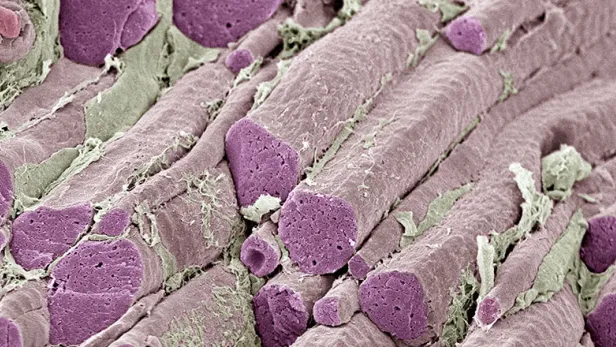

ATTR-CM is a condition in which a specific protein accumulates in the heart, nerves, and other organs. This accumulation can stiffen the heart walls, hardening the left ventricle of the heart. This is called cardiomyopathy, which can cause heart failure.8